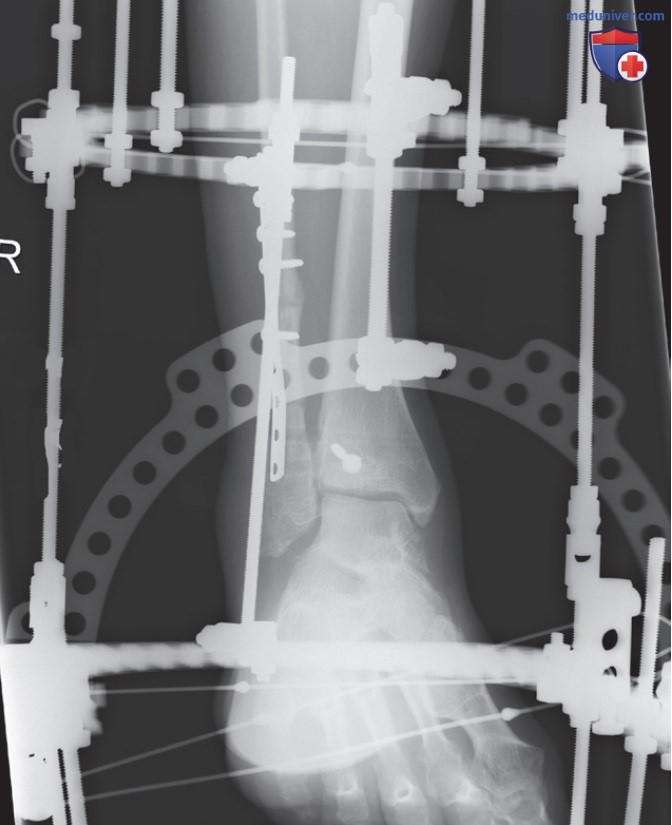

Пространственное разрешение рентгенограммы при оценке ее качества

Рисунок 6. Рентгенограмма правого голеностопного сустава в ПЗ проекции, полученная при большом РОПИ вследствие наличия спице-стержневого аппарата. В нестандартных клинических ситуациях рентгенолог может оказаться не в состоянии установить часть тела как можно ближе к ПИ. Например, в тех случаях, когда пациент не может разогнуть коленный сустав для рентгенографии в ПЗ проекции, или когда пациенту проводится вытяжение, как показано на этой рентгенограмме. В этом случае голеностопный сустав будет располагаться далеко от ПИ, и уменьшить РОПИ будет невозможно. Чтобы предотвратить проекционное увеличение, можно увеличить РИПИ, оставив соотношение между РИПИ и РОПИ неизменным. Проекционное увеличение объекта при РОПИ 2,5 см и РИПИ 100 см будет таким же, как и при РОПИ 10 см и РИПИ 400 см, поскольку сохраняется соотношение 1:40. Однако добиться полной компенсации проекционного увеличения часто не удается, поскольку РИПИ имеет свой предел.